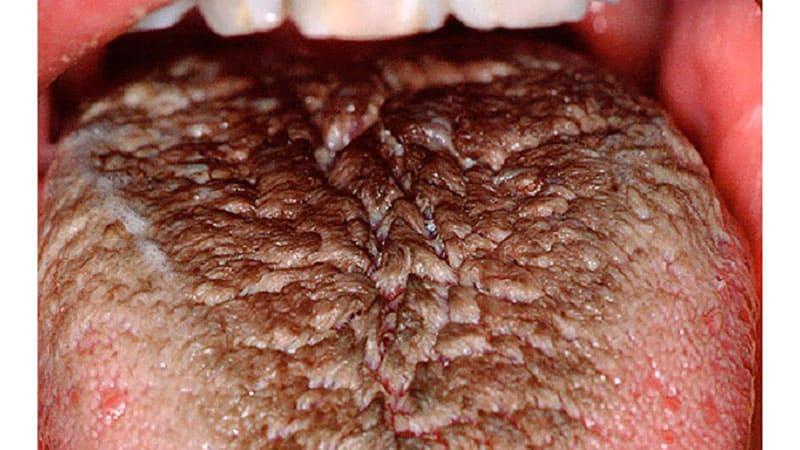

Коричневый налет на языке — симптом, вызывающий беспокойство у взрослых и детей. Он может указывать на заболевания, нарушения гигиены полости рта, пищеварительные проблемы или инфекции. В статье рассмотрим основные причины коричневого налета, его симптомы и методы лечения, что поможет лучше понять ситуацию и принять меры для восстановления здоровья. Знание этих аспектов позволит своевременно обратиться к врачу и избежать осложнений.

Коричневый налет на языке может возникать по различным причинам. Это может быть связано как с простыми факторами, такими как цвет пищи, которую вы употребляете, так и служить тревожным сигналом о наличии заболевания. Часто изменение цвета языка указывает на проблемы с органами пищеварения. Обычно по оттенку и интенсивности налета можно сделать вывод о степени развития болезни.

Врачи отмечают, что коричневый налет на языке может возникать по нескольким причинам. Одной из основных является недостаточная гигиена полости рта. Накопление бактерий, остатков пищи и мертвых клеток может привести к образованию налета. Также специалисты указывают на влияние определенных продуктов, таких как кофе, чай и табак, которые могут окрашивать язык. Кроме того, коричневый налет может быть признаком заболеваний, таких как кандидоз или гастрит, что требует внимания и консультации врача. Важно помнить, что регулярная чистка языка и соблюдение гигиенических норм помогут предотвратить его появление и поддерживать здоровье полости рта.

Если же налет имеет темный оттенок, его трудно удалить даже при тщательной гигиене, а спустя несколько часов он вновь появляется – это серьезный повод для беспокойства! Потемнение кончика языка может указывать на проблемы с дыхательной системой, а налет на корне языка сигнализирует о возможных нарушениях в пищеварительном тракте.